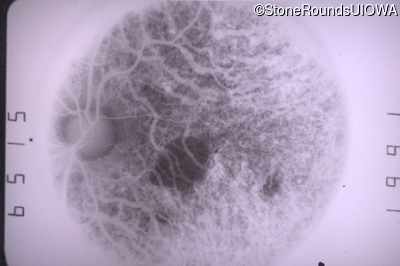

Fluorescein Angiography - Left - 20/40 -2 sc

Exemplar